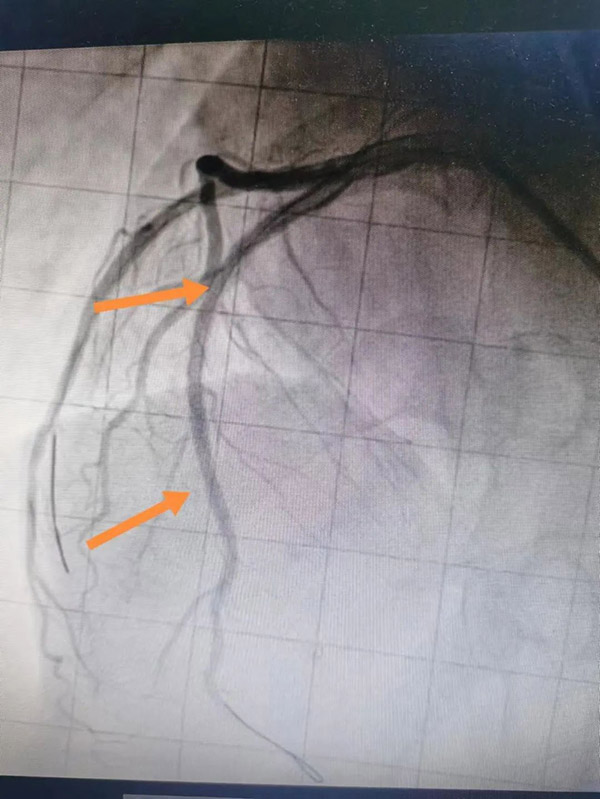

术前 术后

15时34分,患者被推入导管室,虽然已经做了术前评估和心理准备,但一到实操,大家还是如履薄冰。在佟主任带领下,团队充分发挥协作精神,改变惯有思维,谨慎操作。冠脉造影示:主要血管LAD开口90%狭窄,狭窄后100%闭塞,佟主任经慎重考量,经冠脉内溶栓及血栓抽吸,最后在LAD中远端置入支架一枚,血管顺利开通,TIMI血流3级,患者转危为安,大家如释重负。 术后患者被转入CCU病房,李海宁主任带领重症医学团队给予密切观察及术后精准治疗,使患者平稳度过危险期!3天后,患者安返普通病房,“太感谢你们了,是你们把我妈从鬼门关拉回来了啊”,每当管床医生李宏泽、护士长杨天舒查房时,李阿姨的孩子就兴奋对医生护士表示感谢。